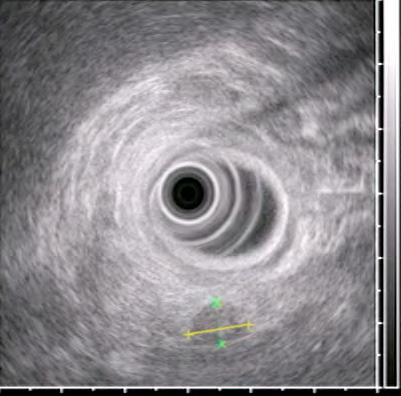

- Endoskopik USM kiçik törəmələrin və limfatik yayılmanın təyinində KT-dən daha həssasdır və mərhələnin təyini üçün istifadə edilə bilər.

- Endoskopik USM (ən həssas müayinədir)

Lokalizasiyanın təyini üçün kontrastlı KT, MRT, endoskopik USM, sekretin reseptoru izotop müayinəsi, əməliyyatdaxili USM aparılır.